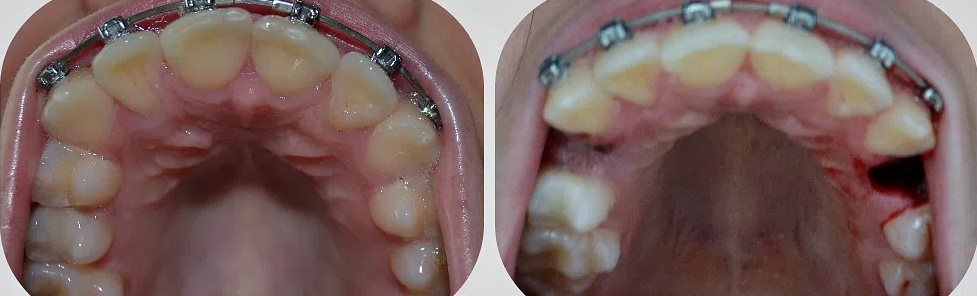

Удаление зубов: фото до и после